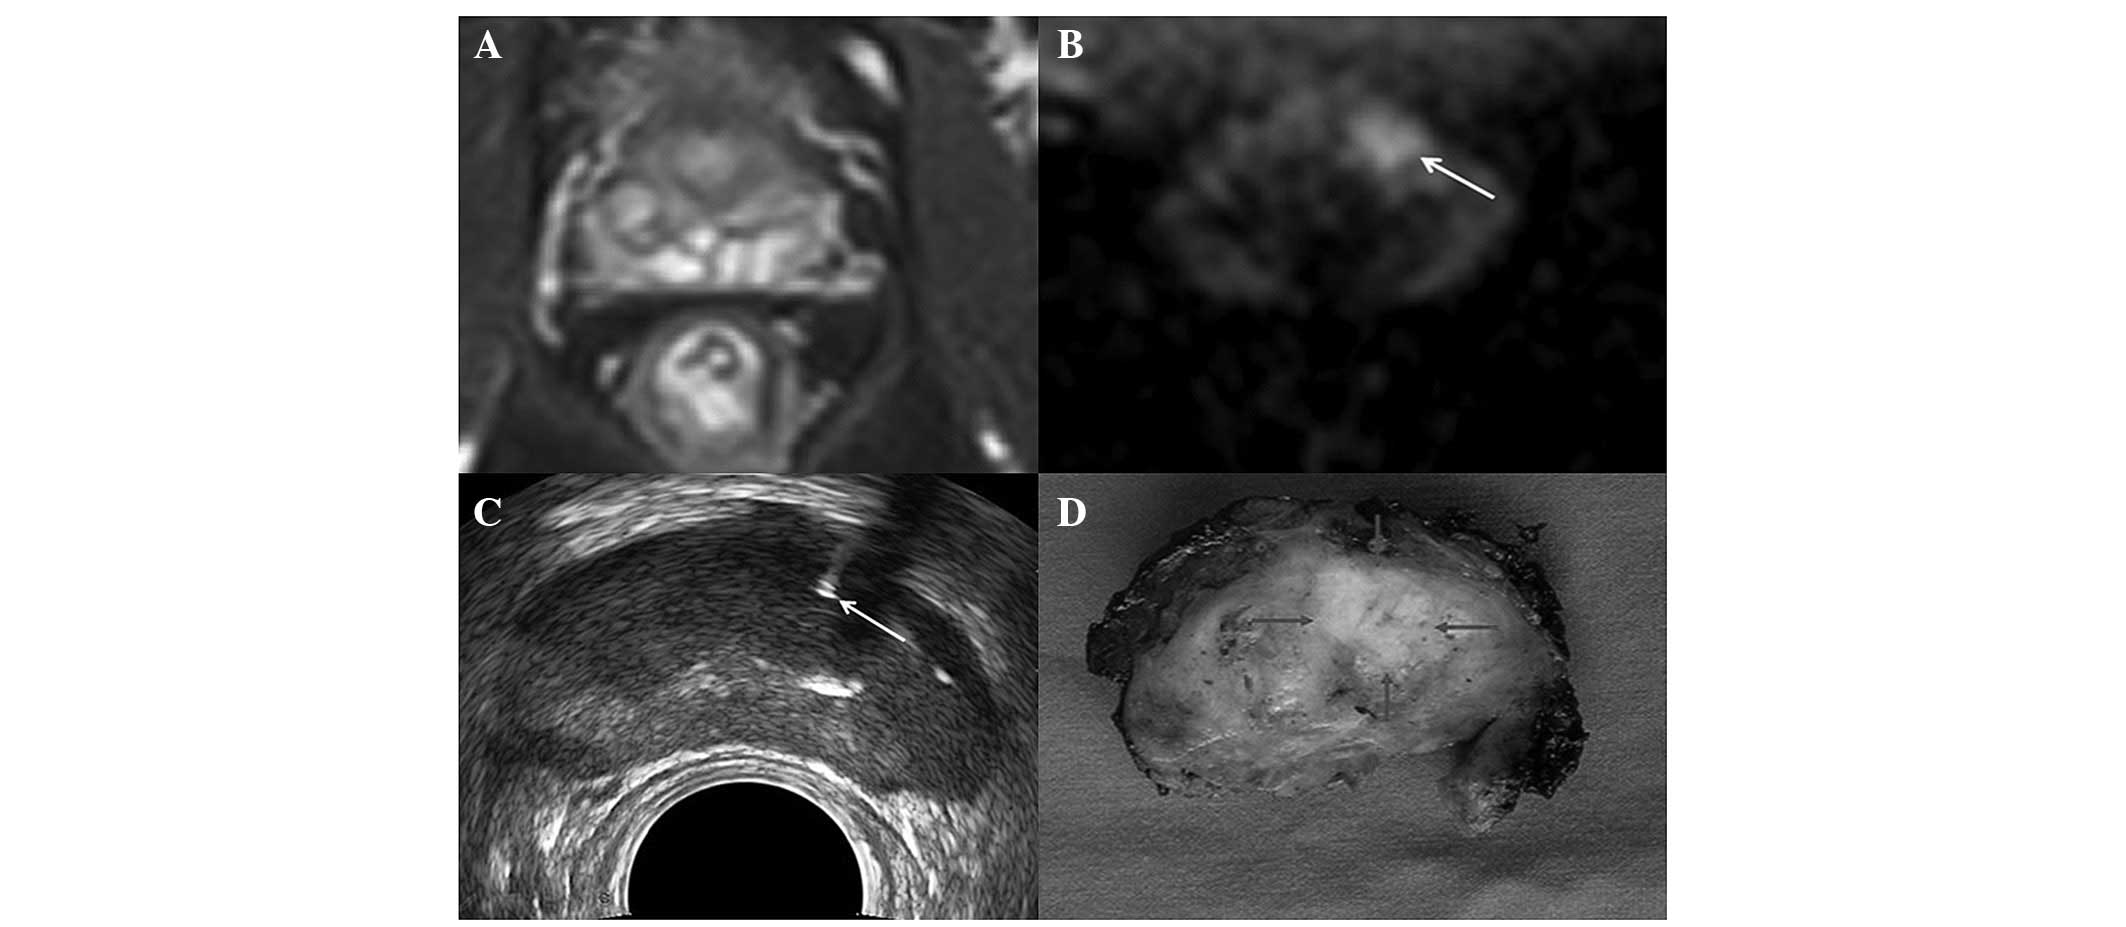

Clinical characteristics of the 420 patients are presented in Table I. PCa was detected in 173 patients (41.2%, 173/420). Among these 173 patients, 41 patients (23.7%, 41/173) were detected by targeted biopsy, but not by systematic biopsy (Fig. 1); 28 patients (16.2%, 28/173) were detected by systematic biopsy, but not by targeted biopsy, and 104 patients (60.1%, 104/173) were detected by both systematic biopsy and targeted biopsy. The increase in the cancer detection rate by targeted biopsy identified by MRI was 9.8% (41/420; P=0.0033). As shown in Table II, among the three groups with PCa detected by different biopsy regimens there were significant differences in serum PSA level, PSAD, prostate volume, DRE findings and TRUS findings, but no differences in age and the biopsy Gleason score.

Figure 1

Images obtained from a 68-year-old patient with a PSA level of 8.4 ng/ml. (A) T2W SPAIR showed no suspicious area in the gland. (B) DWI (arrow) showed a hyperintense area in the left transition zone, which was considered suspicious. (C) TRUS-guided prostate biopsy (arrow) in the suspicious area identified by DWI. (D) Radical prostatectomy specimen (arrow) confirmed the presence of PCa. PSA, prostate-specific antigen; T2W SPAIR, T2-weighted spectral presaturation attenuated inversion recovery; DWI, diffusion-weighted imaging; TRUS, transrectal ultrasound; PCa, prostate cancer.